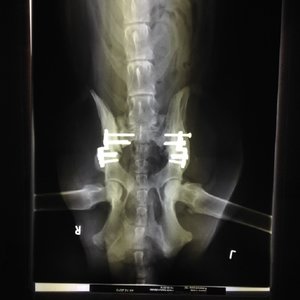

Mal wieder Updates:

Waren heute beim Röntgen. Das Ergebnis: Abby gilt als geheilt und sie darf wieder offline los flitzen :041::026::mrgreen:

Hier mal das Bild dazu. Mein Hund ist jetzt ein Cyborg :lol:

Jetzt ist erst mal Muskelaufbau und Physiotherapie angesagt und ab Februar kann sie wieder ganz die Alte sein (ok, hoffentlich mit besserem Gehorsam als noch im Juli :roll